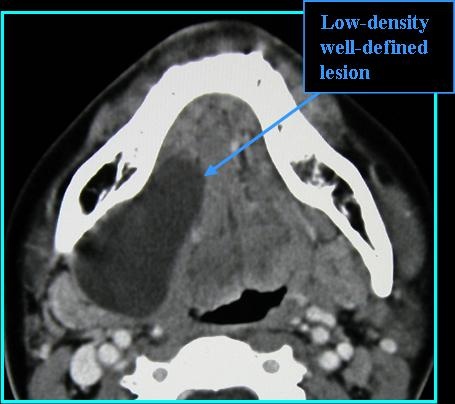

Radiologic Findings

- On CT: low-density, unilocular lesion, subtle ring enhancement, florid enhancement if infected